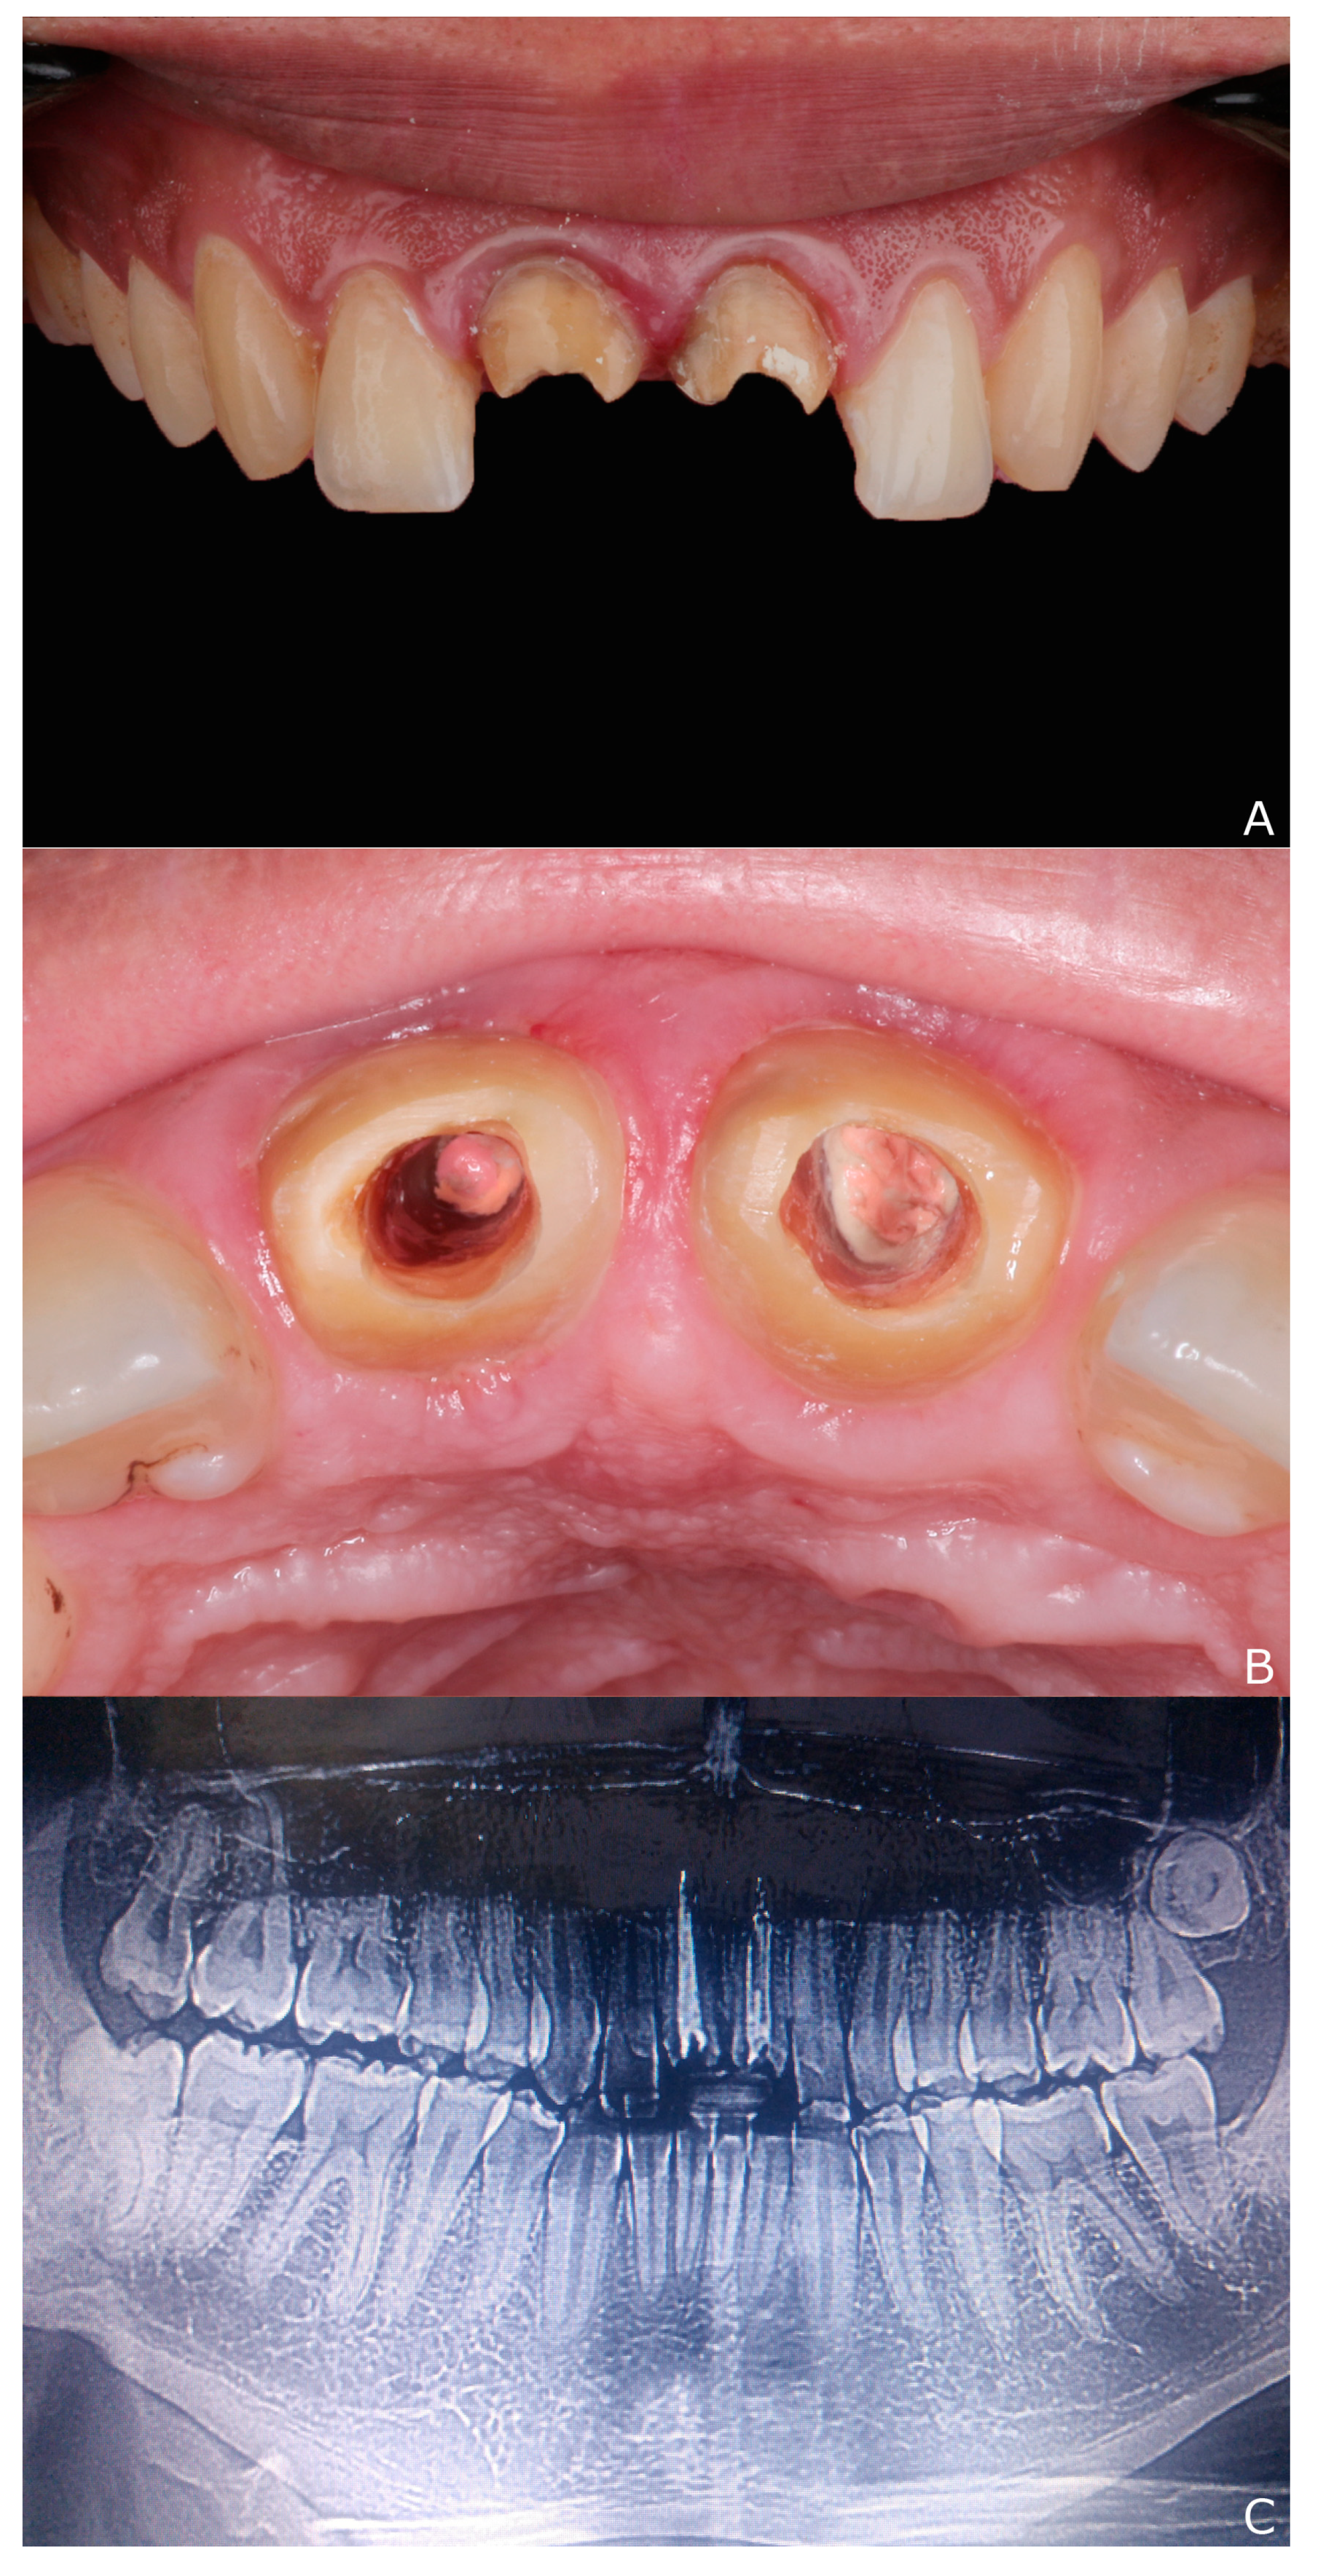

2. Clinical Report